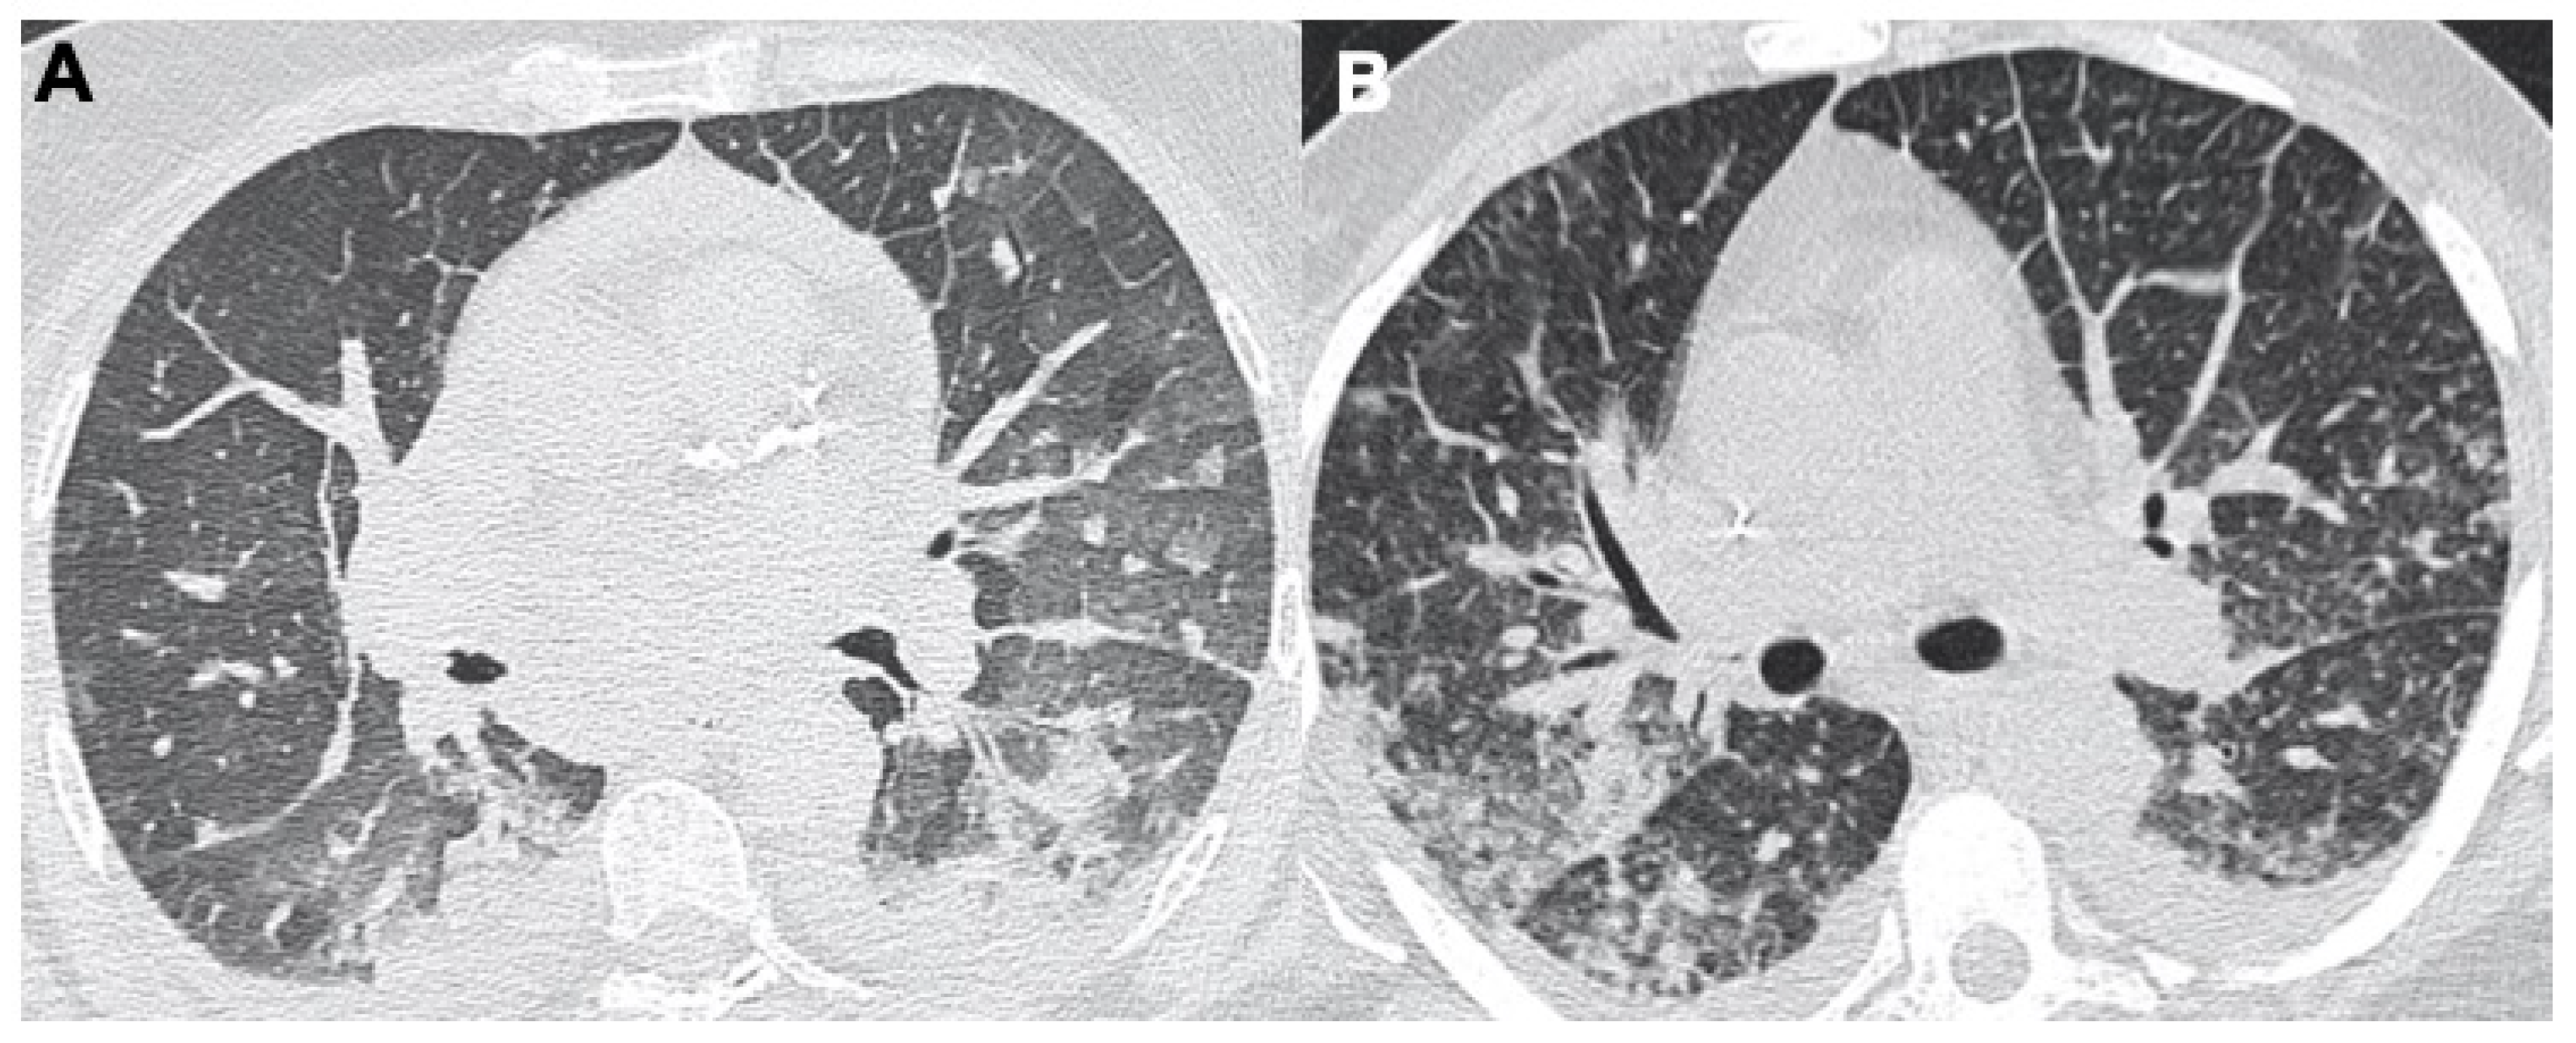

2.1. Pneumonia

2.2. Acute Respiratory Disease Syndrome